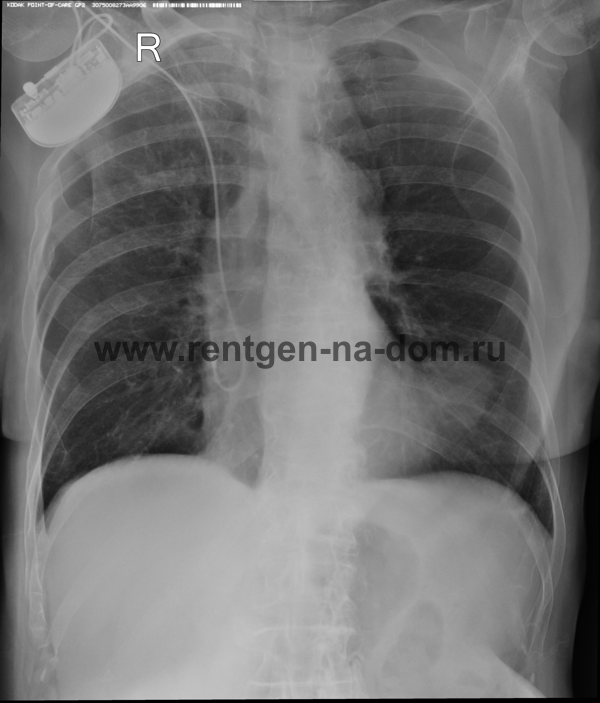

Пневмония – простыми словами воспаление легких – острое воспаление легочной ткани инфекционного происхождения с преимущественным поражением альвеол и интерстициальной ткани легкого. При этом жидкость скапливается в просвете альвеол, что ведет к уменьшению дыхательной поверхности легких. Пневмония может быть самостоятельным заболеванием или быть осложнением другого. Заподозрить пневмонию можно при аускультации (выслушивании) легких при дыхании. Поздняя диагностика и задержка с началом антибактериальной терапии ухудшают прогноз заболевания, возможен летальный исход. Поэтому при малейших подозрениях необходимо сделать рентген легких, особенно пожилым пациентам, а при подтверждении диагноза – поставить вопрос об экстренной госпитализации. Пневмония может лечиться и дома, но такое решение может принять только врач, основываясь на оценке состояния больного, рентгенологической картины легкого и анализов крови. Лечение пневмонии в большинстве случаев требует внутривенного введения антибиотиков, инфузионной терапии (капельниц) и других препаратов. Пациенты, обратившиеся в медицинский центр «Ваше Здоровье», смогут получить весь комплекс необходимых лечебно-диагностических мероприятий, в т.ч. рентген на дому.

Второй наиболее частой причиной, по которой выполняется рентген грудной клетки, является травма груди с подозрением на перелом рёбер. Может показаться, что ушиб грудной клетки является несерьезным основанием, чтобы обратиться к врачу и сделать рентген. Однако приглушая боль приёмом обезболивающих препаратов, можно пропустить ряд опасных осложнений. Сломанные рёбра могут ранить легкое и вызвать пневмоторакс, т.е. скопление воздуха, или гемопневмоторакс, т.е. скопление крови и воздуха в грудной полости. Перелом трех и более рёбер может вызвать серьёзные дыхательные нарушения, что особенно опасно у пожилых пациентов. Поэтому не стоит рисковать здоровьем и необходимо сразу обратиться к врачу. Пациенты, обратившиеся в наш медицинский центр "Ваше Здоровье", смогут получить весь комплекс необходимых лечебно-диагностических мероприятий, в т.ч. рентген на дому.

Получение качественных рентгеновских снимков на дому предъявляет серьёзные требования к рентгеновской аппаратуре. Далеко не каждый переносной рентгенаппарат позволяет получать снимки необходимого качества, чтобы достоверно поставить диагноз. Используемый нами рентгенаппарат АРА 110/160 в комплексе с компьютерным радиографом позволяет получать цифровые рентгеновские снимки высокого качества у пациентов различной комплекции и является уникальной услугой в Санкт-Петербурге, предоставляемой на дому.